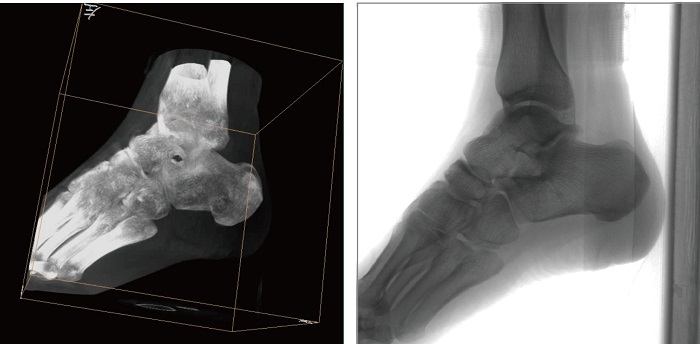

2、创伤外科。例如骨盆骨折内固定术,可术中三维重建髋臼关节面,准确定位并植入螺钉。

3、关节外科。移动式三维小C主要应用于肩关节、肘关节、髋关节、膝关节的关节置换及解剖复位的定位。它可以准确地置入假体。

1、术中三维成像。PLX C7500A三维C型臂的术中三维成像和类CT切片图像提供更全面的手术诊断信息,辅助医生进行术中准确评估判断诸如骨折复位情况和内植入螺钉的尺寸和位置,保证了手术高精度地完成。